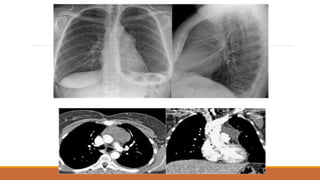

XẸP THÙY DƯỚI(P)

Ít gặp, thường do u chèn ép phế quản trung gian. XQ: xóa bờ tim (P) và vòm hoành (P), rãnh liên thùy lớn (mũi tên đen) và

rãnh liên thùy bé (mũi tên trắng) bị kéo xuống